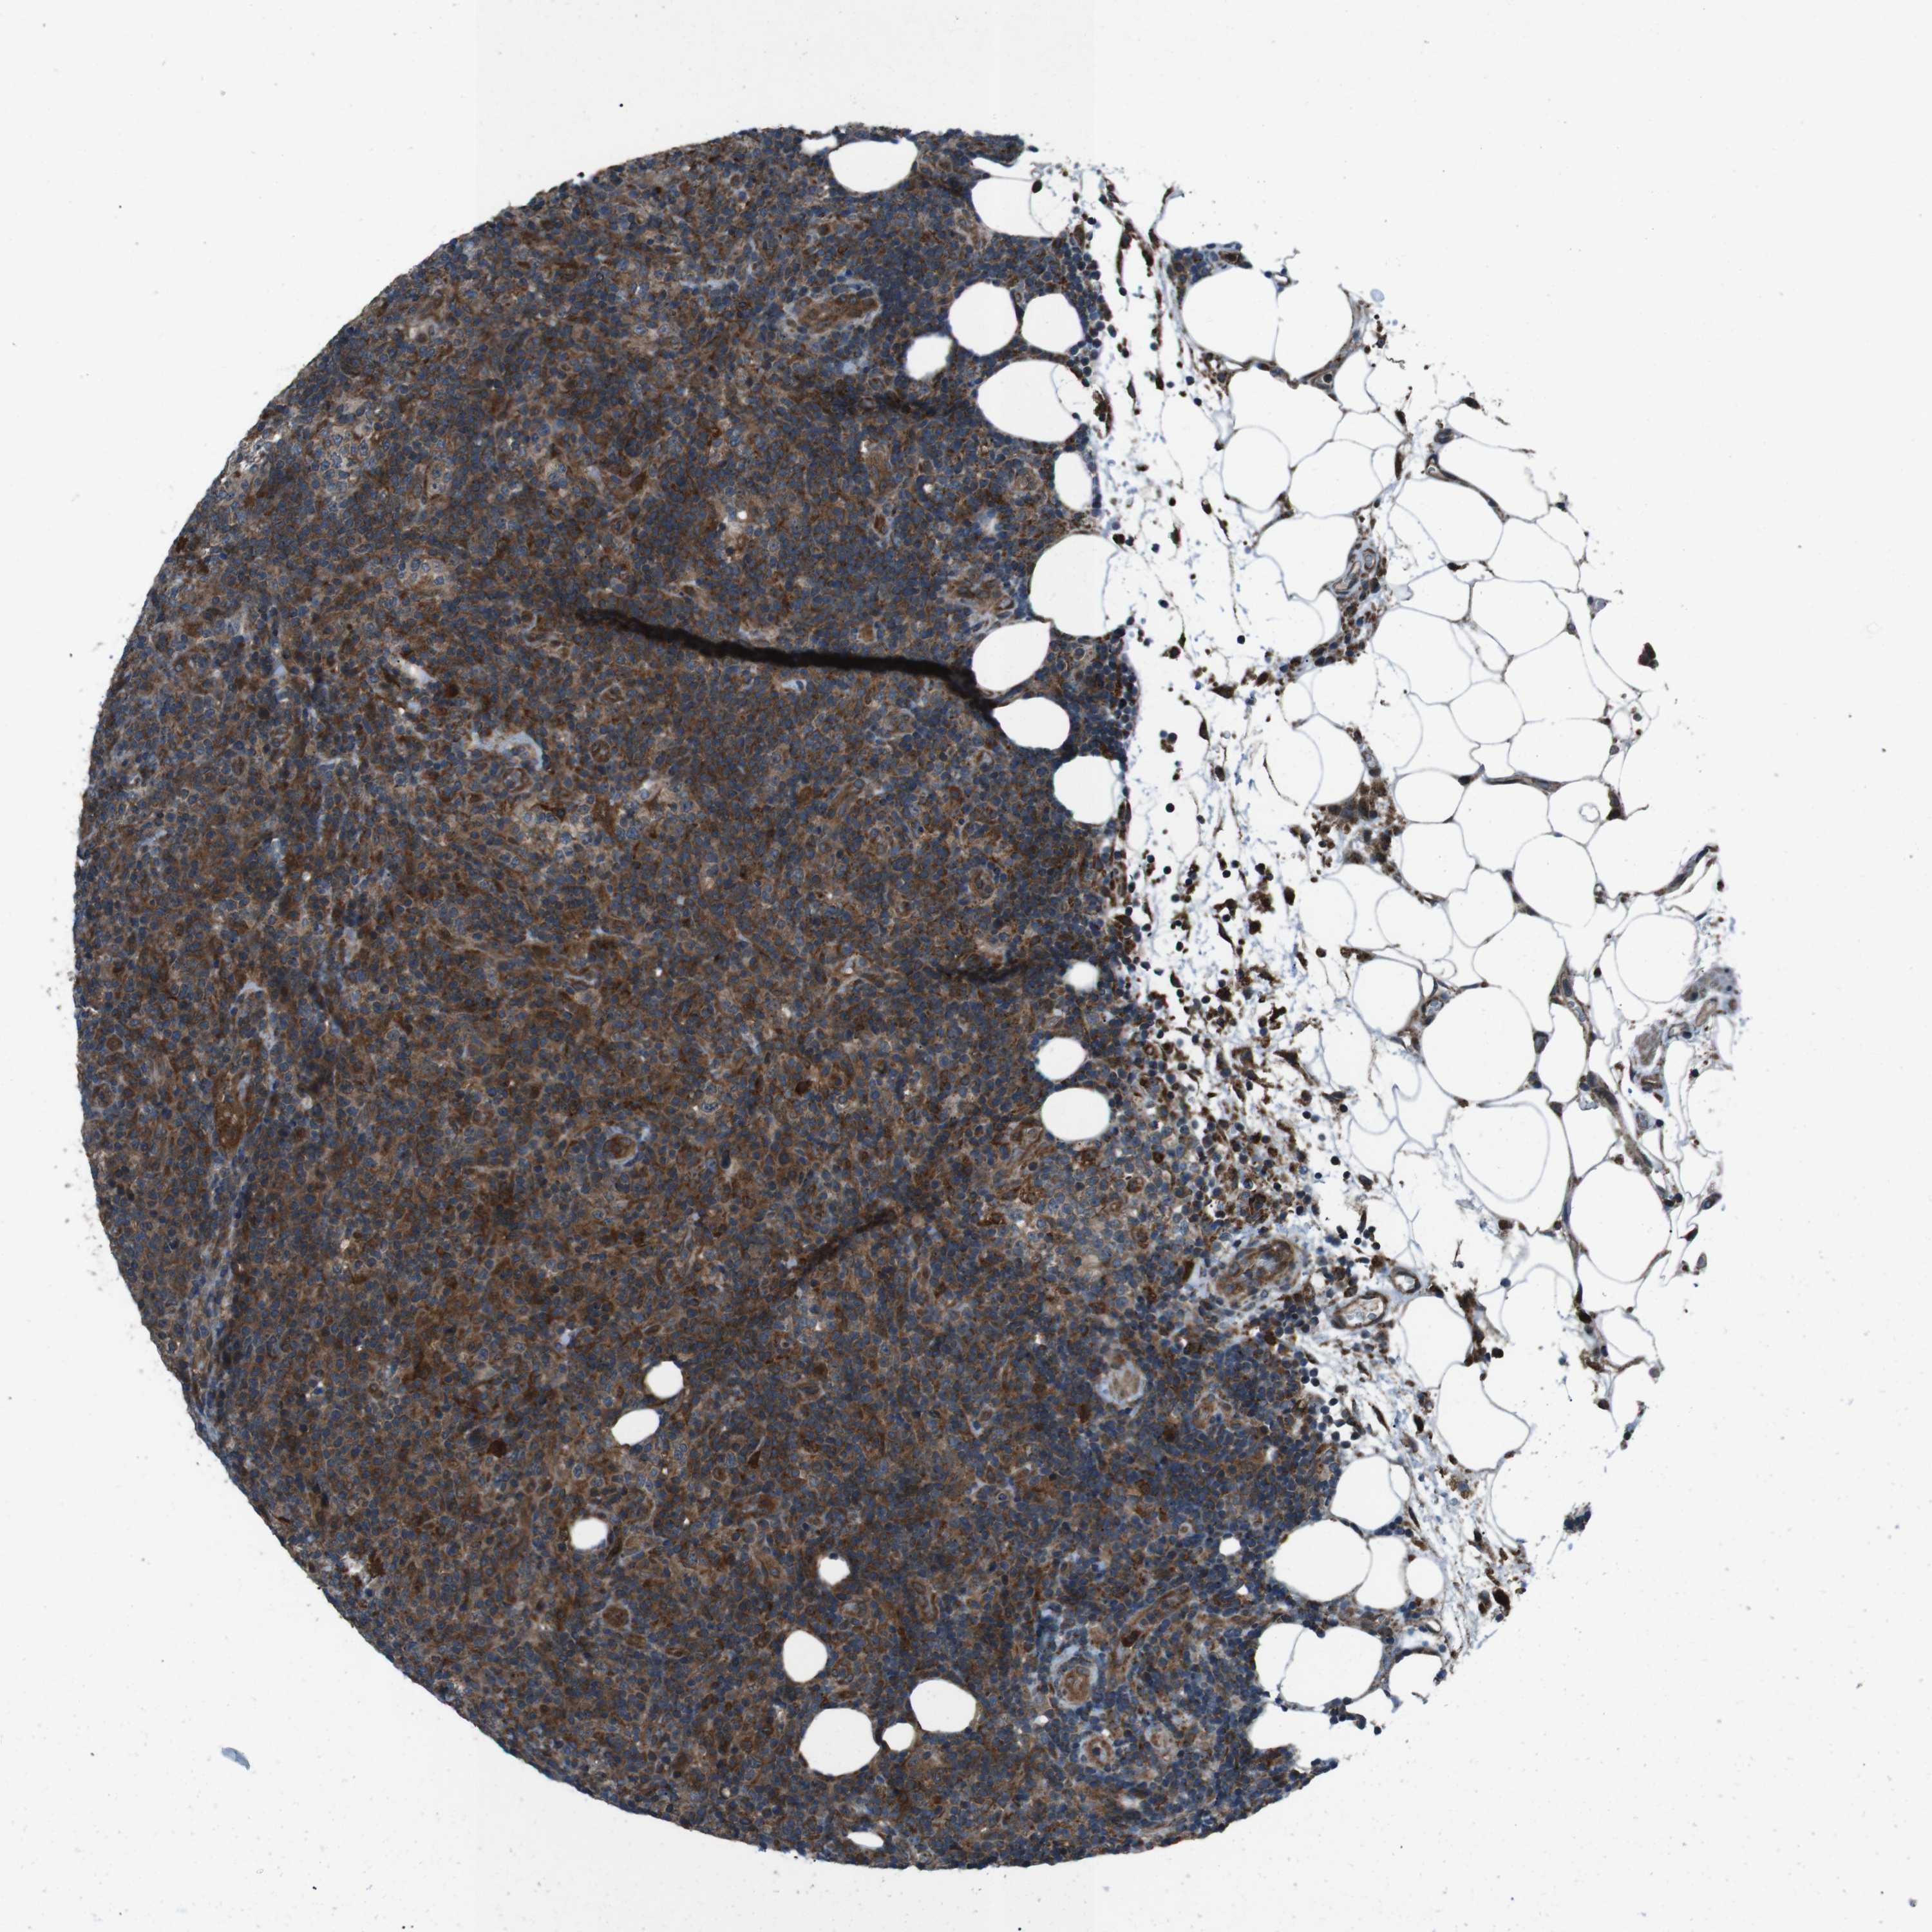

LYMPHOMA - Protein expressioni

A mouse-over function shows sample information and annotation data. Click on an image to view it in a full screen mode. Samples can be filtered based on level of antibody staining by selecting one or several of the following categories: high, medium, low and not detected. The assay and annotation is described here.

Antibody stainingi

Antibody staining in the annotated cell types in the current human tissue is reported as not detected, low, medium, or high, based on conventional immunohistochemistry profiling in selected tissues. This score is based on the combination of the staining intensity and fraction of stained cells.

Each image is clickable and will lead to virtual microscopy that enables deeper exploration of all samples and also displays staining intensity scores, fraction scores and subcellular localization as well as patient and tissue information for each sample.

Antibody HPA007293

Antibody CAB009771

Staining

High

Medium

Low

Not detected

Intensity

Strong

Moderate

Weak

Negative

Quantity

>75%

75%-25%

<25%

None

Location

Nuclear

Cytoplasmic/membranous

Cytoplasmic/membranous,nuclear

Hodgkin's disease, NOS

Malignant lymphoma, non-Hodgkin's type, Low grade

Malignant lymphoma, non-Hodgkin's type, High grade